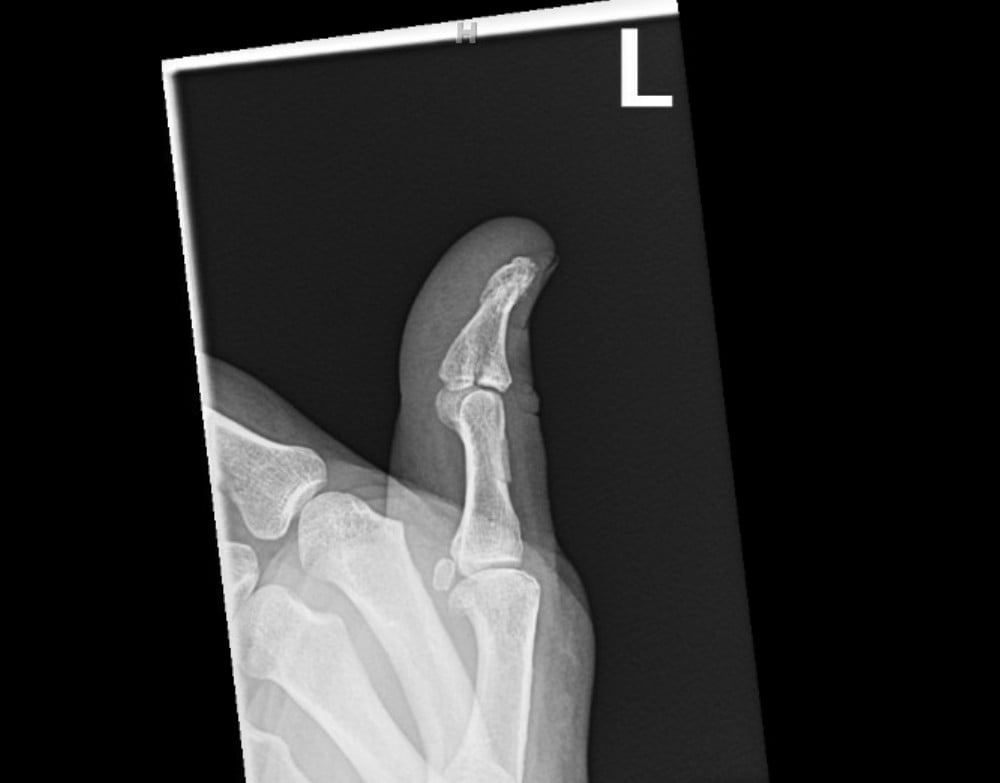

Radiographs were obtained including anterior-posterior and lateral views of the left thumb which demonstrated a penetrating injury of a metallic object (in this case, the threaded nail). The nail on X-ray did appear to pierce the base of the distal phalanx with extension through the interphalangeal joint into the thumb proximal phalanx with an associated vertically oriented split fracture of the proximal phalanx, evident with increased radiolucency on these films. No gas within the soft tissues or other identified foreign bodies; fractures, dislocation, or other acute bony abnormalities were noted. The hospital site has an orthopedic surgery residency program, and the orthopedic surgery resident was consulted given the bony involvement and the recommended outpatient management with an orthopedic hand surgeon.

Post-foreign body removal with cast application X-rays were obtained which redemonstrated the vertically oriented, longitudinal fracture of the left thumb proximal phalanx extending into the interphalangeal joint. Removal of the foreign metal nail also allowed for appreciation of an intra-articular fracture at the distal ulnar aspect of the proximal phalanx where the metallic nail had been previously located, and a distal phalanx base fracture as well. No retained metallic foreign bodies were identified. Of note, there was no involvement of the metacarpal phalangeal joint of the thumb, making this an isolated injury involving only a single joint of the thumb.